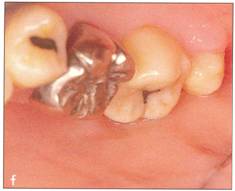

Fi 545e45f g 5-4f Extracted second molar, which will be discarded. Fi 545e45f g Extracted donor tooth. The amount of periodontalligament is adequate. Transplantation was performed 6 weeks after extraction of the tooth from the recipient site. Fi 545e45f g 5-4h View of the donor site and preparation of the recipient site. |

Fi 545e45f g 5-4i After the gingival flap has been sutured and the donor tooth has been splinted. The distal aspect of the donor tooth is closed as tightly as possible. Fi 545e45f g 5-4j After transplantation. Fi 545e45f g 5-4k Two weeks after trans plantation |